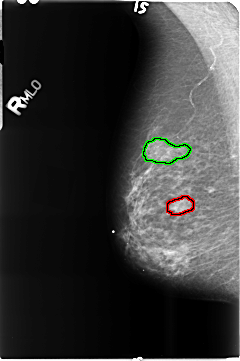

FILE: B_3515_1.RIGHT_MLO.OVERLAY

TOTAL_ABNORMALITIES 2

ABNORMALITY 1

LESION_TYPE MASS SHAPE N/A MARGINS N/A

ASSESSMENT 0

SUBTLETY 0

PATHOLOGY BENIGN

TOTAL_OUTLINES 1

BOUNDARY

ABNORMALITY 2

LESION_TYPE CALCIFICATION TYPE PLEOMORPHIC DISTRIBUTION CLUSTERED

ASSESSMENT 4

SUBTLETY 3

PATHOLOGY MALIGNANT